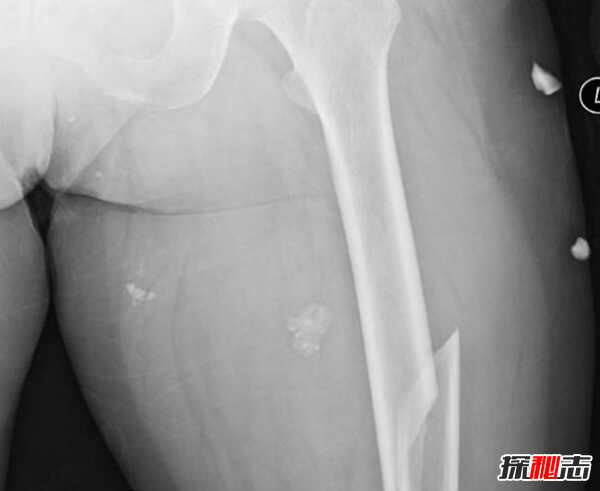

7、股骨骨折

股骨或大腿骨是人体中最大的骨骼,股骨骨折是人们可能经历的最痛苦的骨折。 即使在愈合过程中也是艰巨的,通常需要四到五个月的时间,并且在恢复多年后可能会受到某些因素的持续影响。